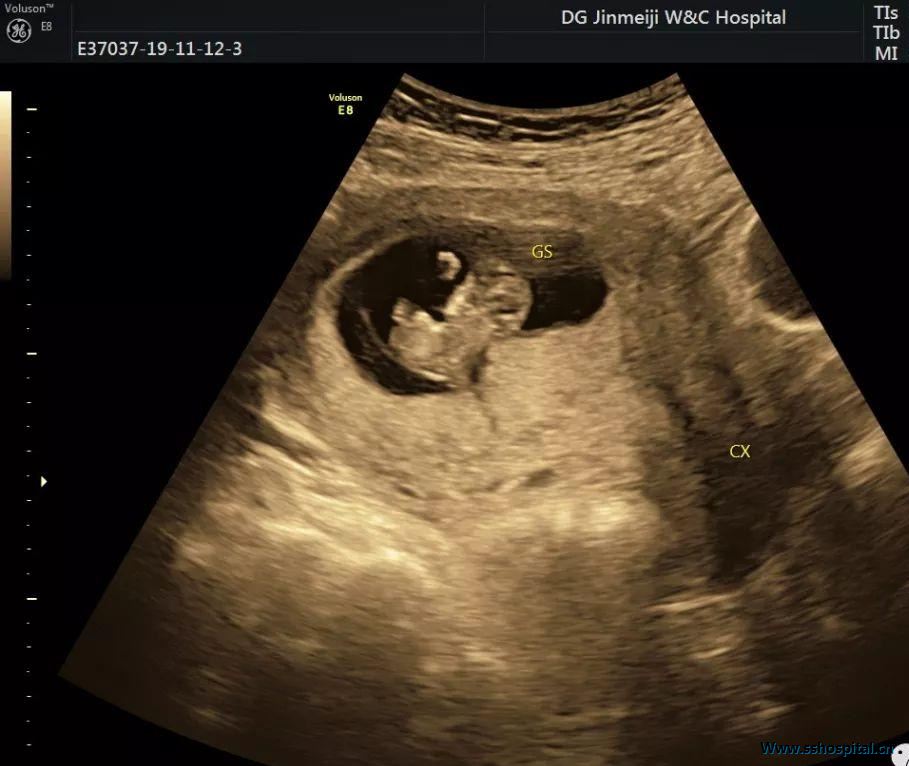

子宫呈极度后倾后屈位,宫颈管细长;宫体位于宫颈后方,宫底平宫颈外口水平;宫腔内可见狭长型胎囊,大小 59×18 mm,内见胚胎约 34 mm,并见胎心搏动及卵黄囊(图 1 和图 2)。

超声提示:宫内早孕,约孕10周;子宫形态超声改变,考虑妊娠子宫箝闭;尿潴留。

图 1 下腹部纵切面示细长的宫颈(CX)位于宫体上方,宫底(红箭头)与宫颈外口(蓝箭头)同一水平

临床将患者收入住院,立即给予导尿,约 900 ml,并留置导尿管。常规实验室检查未见异常。临床医师采用手法复位(排空患者膀胱,取膀胱截石位,医师一手的两手指置于******后穹窿向上推子宫底,另一手放于腹部逐步探及宫底,两手一起复位),后复查超声,发现子宫、宫颈和宫内孕囊均恢复正常形状(图 3 和图 4)。

图 3 经手法复位后,子宫、宫颈恢复正常形状